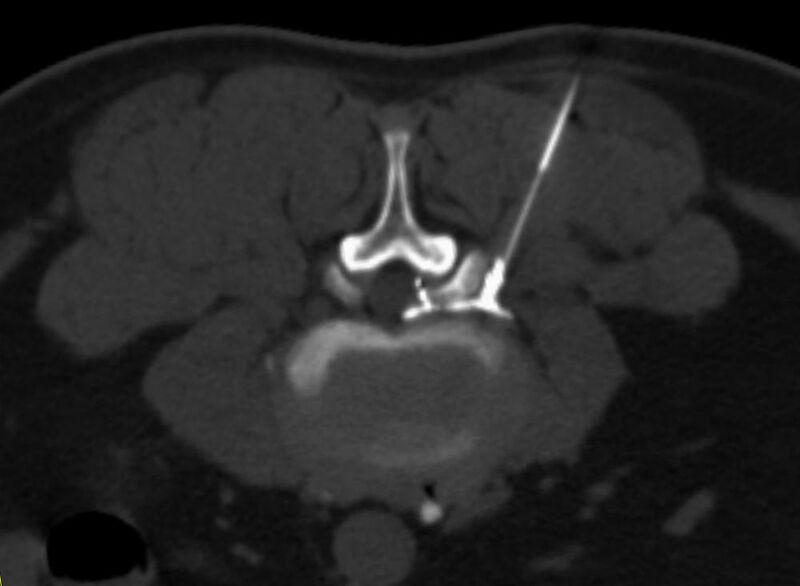

Interventionelle Eingriffe

Durchführung am Standort im Diakonissenkrankenhaus

• z. B. Punktionen zur Gewebsentnahme

Schmerztherapie

(dazu mehr auf der Seite Schmerztherapie)

Der Multislice-Scanner ermöglicht eine dem aktuellen Stand der Technik entsprechende, leitliniengerechte diagnostische Untersuchung sämtlicher Körperregionen. Darüber hinaus gestattet der neue Computertomograph auch eine für Arzt und Patient bequeme Durchführung CT-gestützter Interventionen wie z.B. Schmerztherapien der Wirbelsäule.